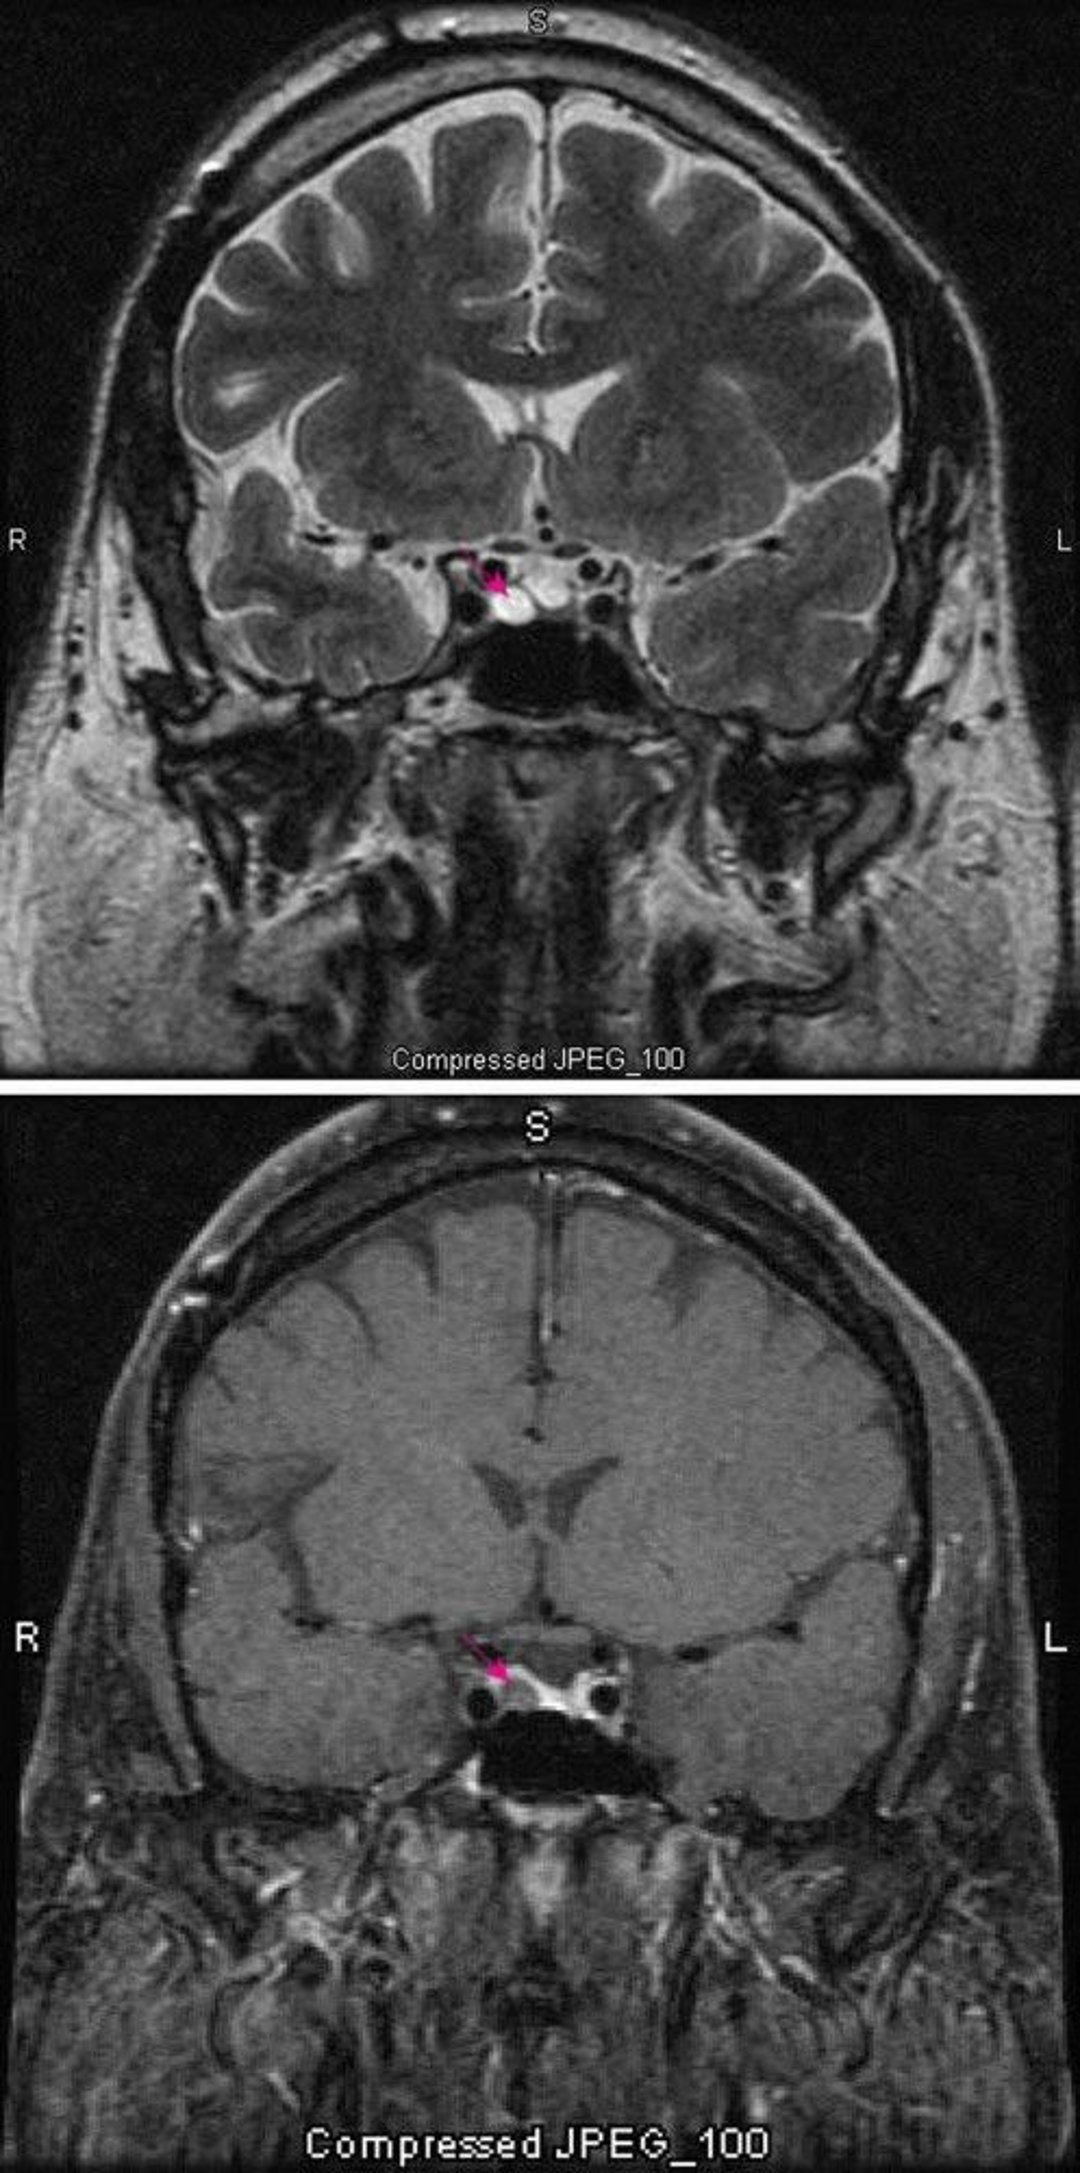

T2-weighted MRI scan (top) shows a pituitary microadenoma (red arrow). Contrast (bottom) normally enhances the pituitary (red arrow). The adenoma appears lighter.

Images courtesy of William R. Shapiro, MD.